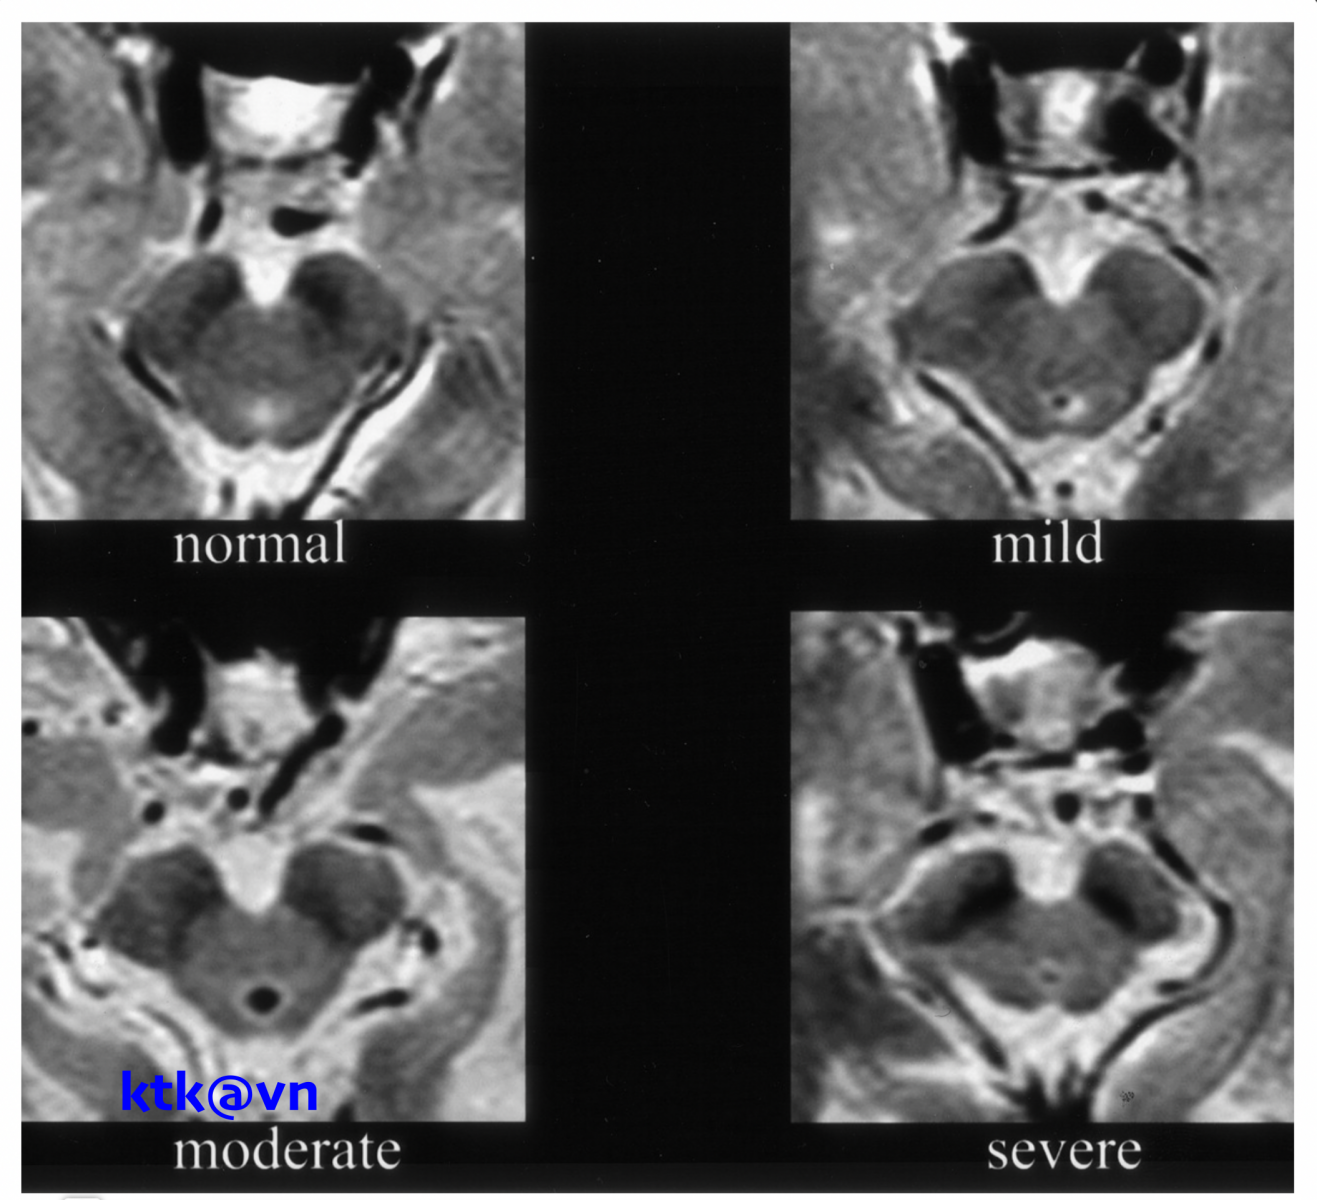

Những đặc điểm thường gặp trên hình ảnh phim chụp cộng hưởng từ sọ não là teo não giữa, giãn não thất ba, teo cuống tiểu não trên (SCP), teo thùy trán và thái dương. Teo não giữa được thể hiện trực quan qua hình ảnh “mỏ chim ruồi” khi nhìn trên lát cắt đứng dọc, hình ảnh “chuột Mickey” khi nhìn trên lát cắt ngang, hình ảnh “morning glory” (một số tài liệu gọi là dấu hiệu hoa mòng biển) trên lát cắt ngang. Teo cuống tiểu não trên, dấu hiệu “chim ruồi”, dấu hiệu “hoa mòng biển” trên cộng hưởng từ cấu trúc có độ đặc hiệu cao nhưng độ nhạy kém hơn tiêu chuẩn lâm sàng.